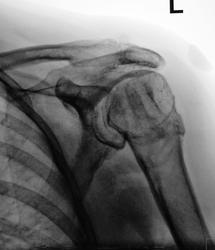

Головка плеча в состоянии шиворот - навыворот с подвывихом вверх.

Видимо, был переломо-вывих плеча.

Травма была...

но пациентка за медпомощью не обращалась, хотя плечо болело...

Сделали снимок чуть бочком...

Жидкость в сумке? Вот тут точно УЗИ.

Если Вы о тени в мягких тканях, так то огромная родинка.